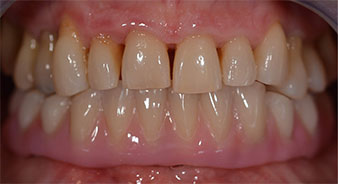

The 64-year-old patient presented with residual dentition of teeth 38, 33 and 43 and a clasp denture in the mandible (Fig. 1 and 2).

residual dentition

Fig. 1

Fig. 2